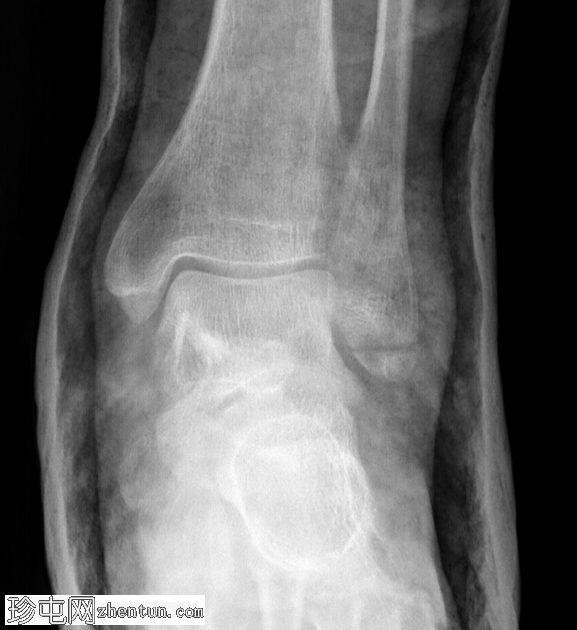

X光片

斜位

胫腓联合下方外踝完全横向骨折,石膏固定复位。

左脚韦伯A型外踝骨折石膏固定复位后的随访X光片。